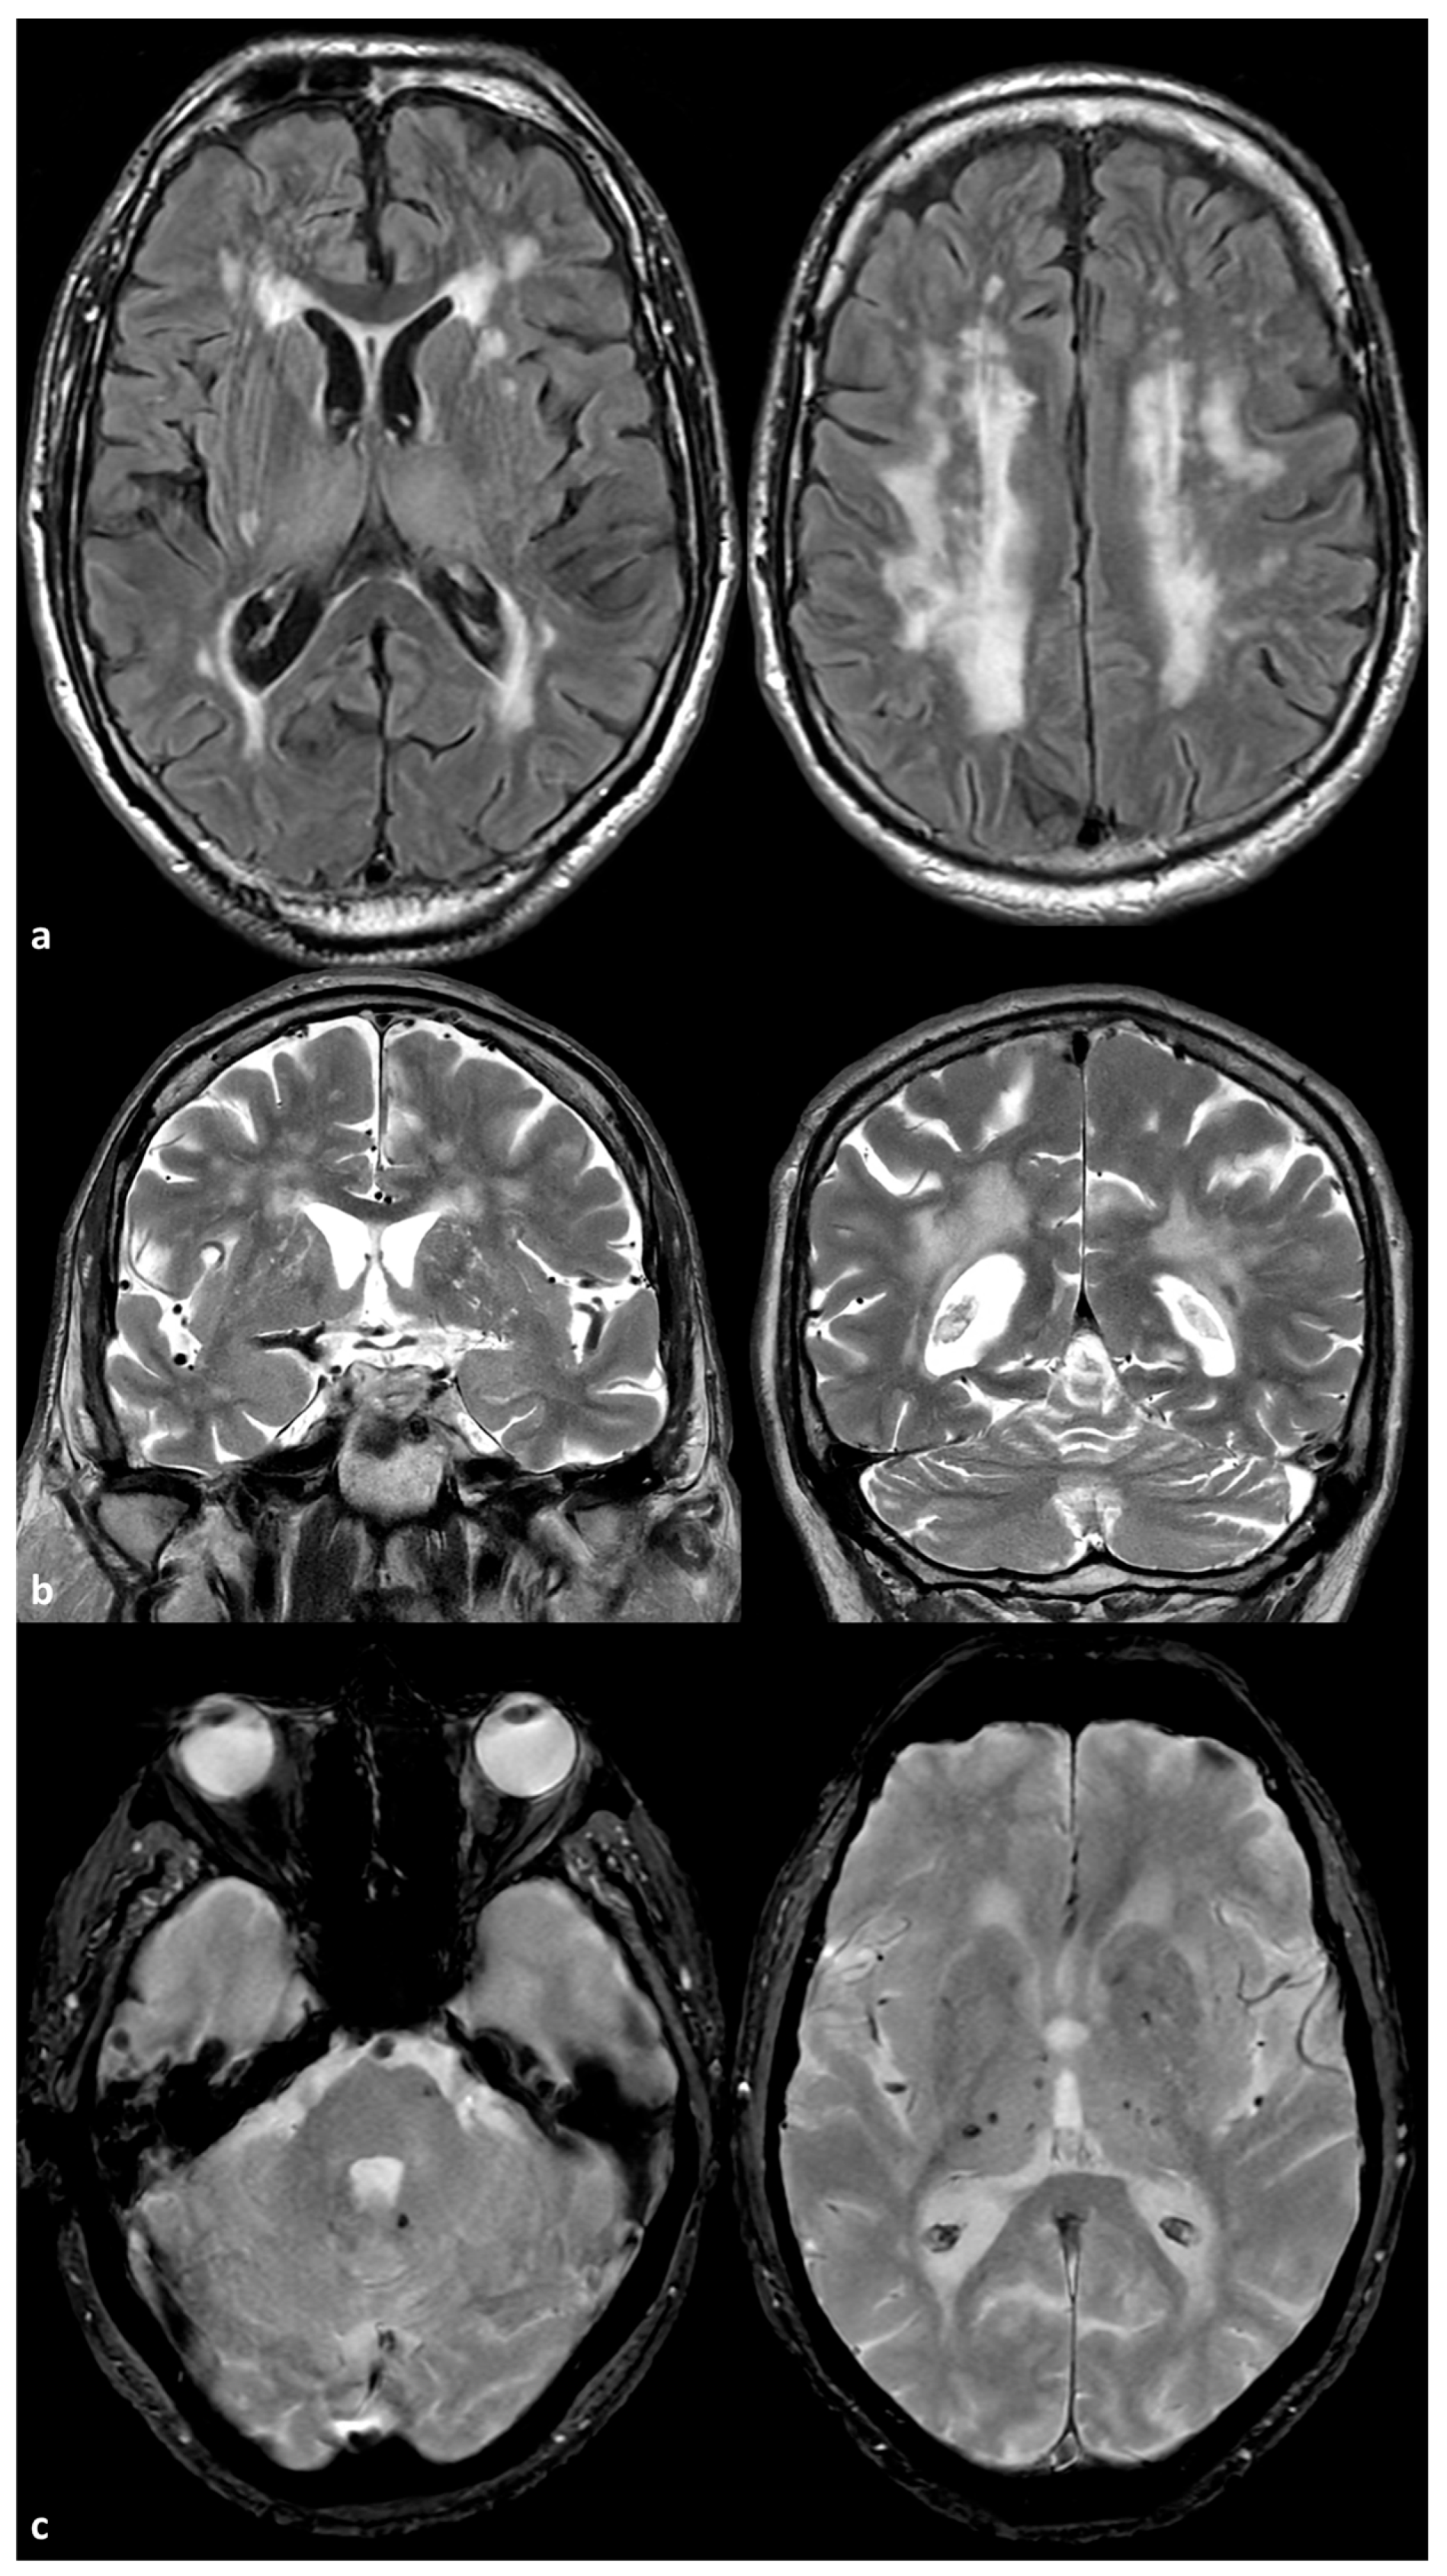

- Duering, M.; Biessels, G.J.; Brodtmann, A.; Chen, C.; Cordonnier, C.; de Leeuw, F.-E.; Debette, S.; Frayne, R.; Jouvent, E.; Rost, N.S.; et al. Neuroimaging standards for research into small vessel disease—Advances since 2013. Lancet Neurol. 2023, 22, 602–618. [Google Scholar] [CrossRef]

- Uemura, M.; Hatano, Y.; Nozaki, H.; Ando, S.; Kondo, H.; Hanazono, A.; Iwanaga, A.; Murota, H.; Osakada, Y.; Osaki, M.; et al. High frequency of HTRA1 and ABCC6 mutations in Japanese patients with adult-onset cerebral small vessel disease. J. Neurol. Neurosurg. Psychiatry 2022, 94, 74–81. [Google Scholar] [CrossRef] [PubMed]

- De Vilder, E.Y.; Cardoen, S.; Hosen, M.J.; Le Saux, O.; De Zaeytijd, J.; Leroy, B.P.; De Reuck, J.; Coucke, P.J.; De Paepe, A.; Hemelsoet, D.; et al. Pathogenic variants in the ABCC6 gene are associated with an increased risk for ischemic stroke. Brain Pathol. 2018, 28, 822–831. [Google Scholar] [CrossRef]

- Kauw, F.; Kranenburg, G.; Kappelle, L.J.; Hendrikse, J.; Koek, H.L.; Visseren, F.L.J.; Mali, W.P.T.; de Jong, P.A.; Spiering, W. Cerebral disease in a nationwide Dutch pseudoxanthoma elasticum cohort with a systematic review of the literature. J. Neurol. Sci. 2017, 15, 167–172. [Google Scholar] [CrossRef]